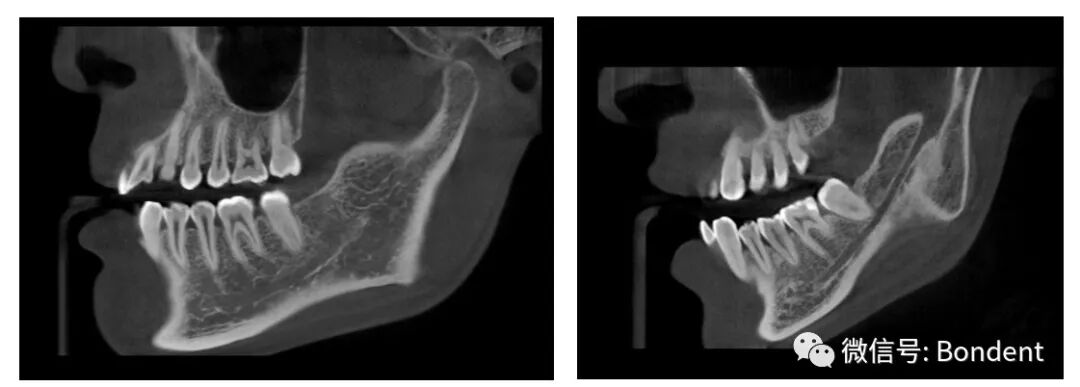

“伯爵Bondream”智能3D全景CBCT 多金屬去偽影圖

普通CBCT 多金屬去偽影圖(同一患者)

上頜竇底,骨小梁與下頜神經(jīng)管清晰可見(jiàn)

植體周圍無(wú)陰影,植體螺紋清晰可見(jiàn)